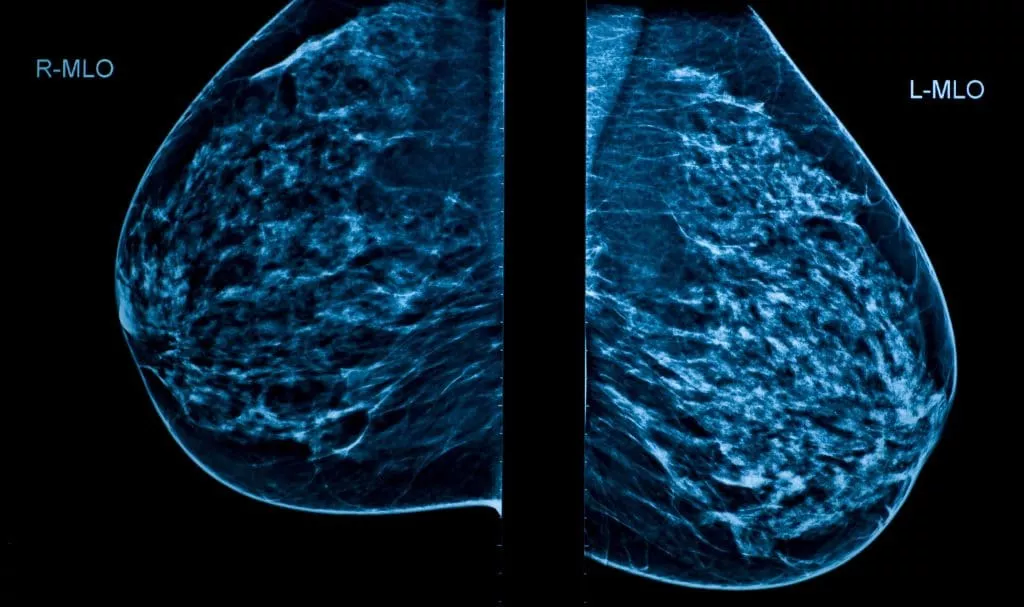

A 3D mammogram is an advanced imaging technique that takes 400 low-dose X-ray images from different angles to create a detailed, three-dimensional view of the breast. This approach provides a more comprehensive picture than traditional 2D mammography, helping radiologists to:

A 3D Mammogram takes up to 400 images of your breast (compared to 4 images in a 2D Mammogram) from different angles to create a detailed, three-dimensional view.